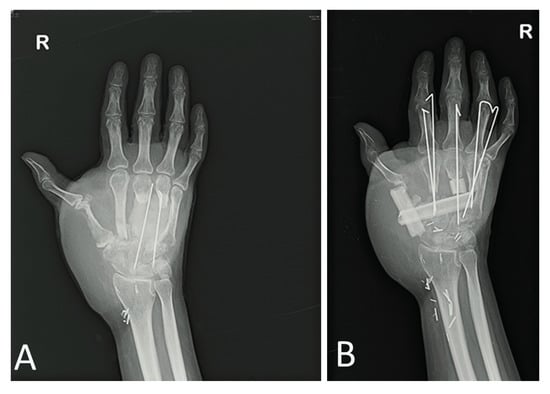

3.1. Case Study #1

3.2. Case Study #2